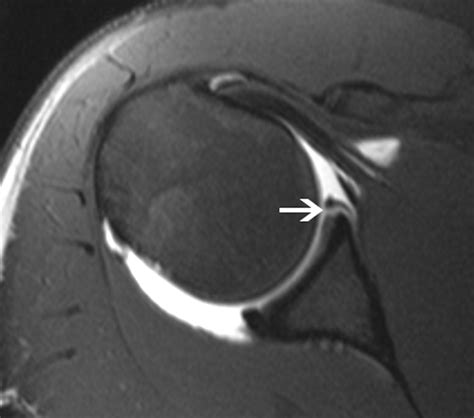

Interpreting the results of a Slap Tear MRI involves a thorough examination of the images by a radiologist. Key findings that indicate a SLAP tear include:

• Abnormal signal intensity within the labrum, suggesting a tear.

• Displacement or detachment of the labrum from the glenoid.

• Fluid or contrast agent extending into the tear, highlighting the extent of the injury.

• Associated injuries, such as rotator cuff tears or biceps tendon pathology.

Radiologists use specific criteria to classify SLAP tears based on their appearance on MRI images. For example, a Type II SLAP tear may show detachment of the labrum and biceps tendon from the glenoid, while a Type IV tear may exhibit a displaced flap of tissue.